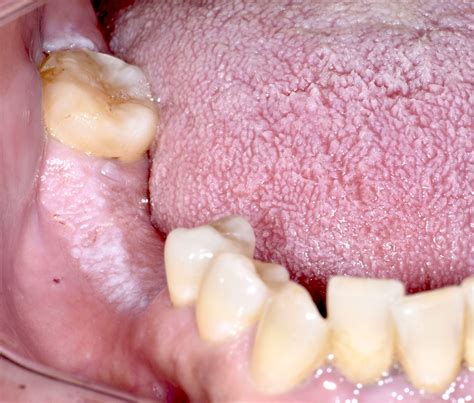

Cheek Linea Alba

Characteristics of the Cheek Linea Alba

The Cheek Linea Alba has several distinct characteristics that help in its identification:

• Appearance: The line is typically white or light-colored and can vary in thickness and length. It often appears on the cheeks, near the nasolabial folds.

• Location: The Cheek Linea Alba is usually found on the cheeks, but it can also appear on other parts of the face, such as the forehead or chin.

Cheek Linea Alba Image